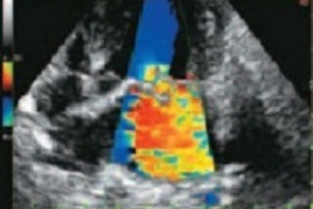

Comment traiter une maladie valvulaire dégénérative en 2021 ? La maladie valvulaire dégénérative est la maladie cardiaque la plus répandue, sa prise en charge fait partie de la pratique régulière du généraliste. Depuis plusieurs années les spécialistes en cardiologie se réunissent pour établir un consensus régulièrement mis jour pour la prise en charge de cette maladie.